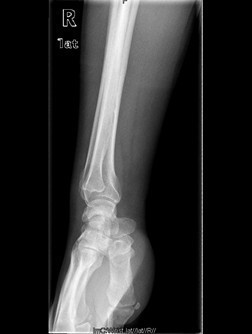

患者男,60岁,因“右腕部疼痛5月,右小指屈曲障碍20天”入院。入院前5月,患者无明显诱因情况下出现右侧腕部尺侧酸痛不适,未就诊治疗。左小指伸曲正常;入院前20天,患者出现右小指屈曲障碍,无小指指麻木,遂来我院治疗,门诊以“左小指深浅屈肌腱迟发性断裂”收入院。

查体:右侧小指伸直位,不能屈曲。右侧腕部尺侧可触及一质韧包块。右小指感觉正常,末梢循环正常。右小指不能主动屈曲掌指关节及中节、末节手指;伸指正常,余手指活动正常。 辅查:彩超示右腕包块处肌腱周围粘稠积液伴滑膜增厚。